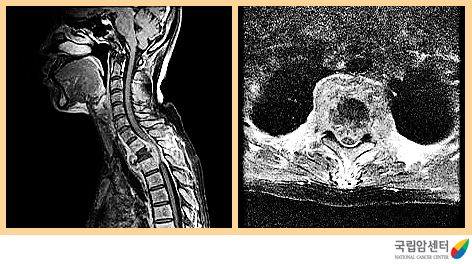

현재까지 진단 방법 중 가장 정확한 방법입니다. 자기공명영상촬영(MRI)은 전산화단층촬영(CT)에 비해 근육, 인대 등의 연부조직의 대조가 뛰어나고 횡단영상 뿐만아니라 관상영상과 시상영상 등 원하는 어떠한 단면의 영상도 얻을 수 있기 때문에 척수종양의 크기나 범위 낭포성 변성을 쉽게 판단할 수 있습니다. 조영증강에 의해 대부분의 병소가 더욱 명확해지며, 다발성 경화증, 척수경색증, 정맥울혈, 출혈, 척수염 등은 자기공명영상(MRI)상 척수의 팽대와 척수내 조영증강되는 음영을 볼 수 있어 종양과의 구별이 어려운 때가 있습니다.

[ 전이성 척수종양의 자기공명 영상촬영 소견 ]